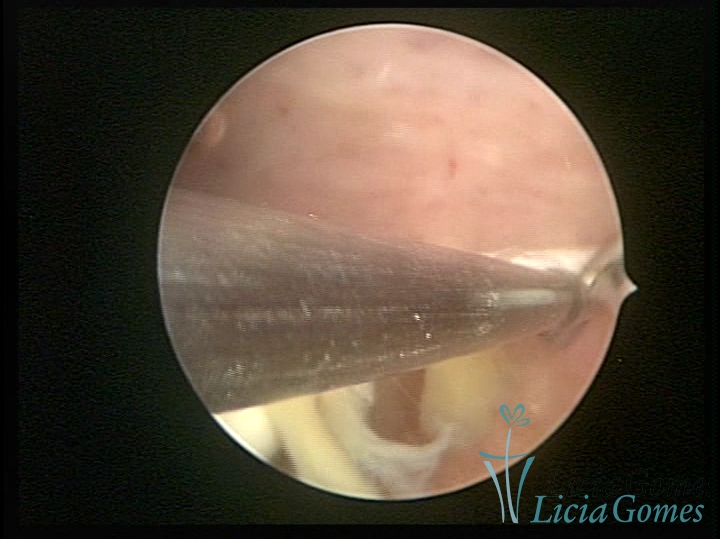

Cicatriz de cesárea com fio de sutura, não absorvido, como corpo estranho